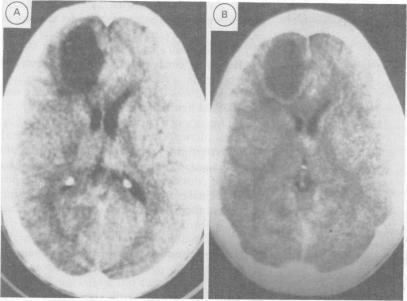

Three cases are presented in which clinical and radiological features suggested the diagnosis of glioma but surgical biopsy revealed a demyelinating process, with tissue destruction and cyst formation in two. One patient had clinically definite multiple sclerosis. Two had probable acute disseminated encephalomyelitis. Treatment with high dose steroids is appropriate when there is clinical or investigative evidence to suggest the presence of demyelinating disease, before deciding on biopsy.

本文报告了3例病例,其临床和影像学特征提示为胶质瘤,但手术活检显示为脱髓鞘病变,其中2例伴有组织破坏和囊肿形成。1例患者临床上确诊为多发性硬化症。2例可能为急性播散性脑脊髓炎。在决定活检之前,当有临床或检查证据提示存在脱髓鞘疾病时,使用大剂量类固醇治疗是合适的。